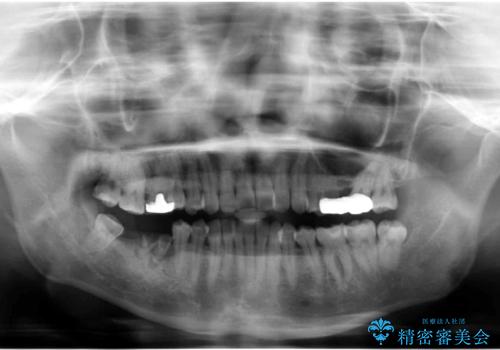

右下は虫歯がひどく、抜歯が必要でした。また、右下の一番奥の歯は親知らずのため使うことができない状態でした。

右上に部分矯正を行い、クリアランスを確保した後、右下にイプラントを2本埋入しています。

上の歯が伸びだしてきていたため、部分矯正を行い歯を移動させてから、向かい合わせの歯にインプラント治療を行っています。

右上第一大臼歯は六本木院の林院長に根管治療をお願いしました。